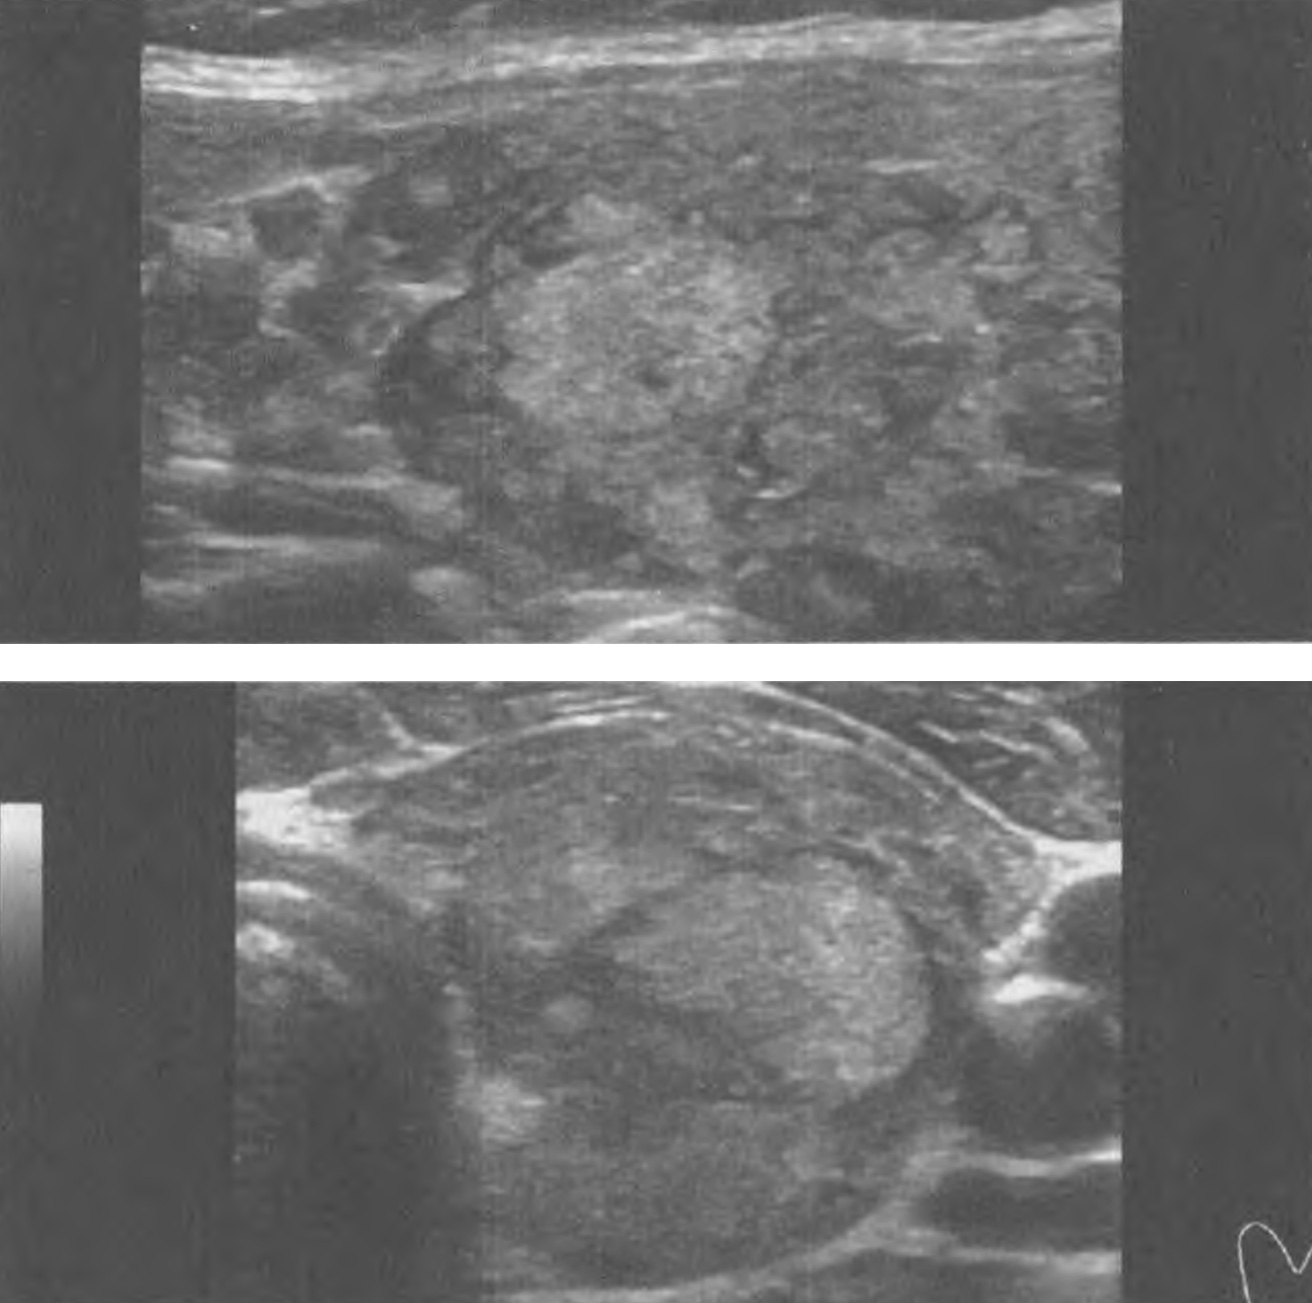

Впрочем, моя зрительная оценка УЗ-примеров (снимков), представленных авторами этого исследования и при которых были допущены ошибки специалистами, быстро выявила признаки рака и доброкачественности, совпавшие с реальностью, что указывает, с одной стороны на недостаточный уровень внимания или знаний специалистов, а с другой – подтверждает способности вспомогательного программного обеспечения (рис. 26, 27). В первом случае (рис. 26) по ACR TI-RADS узлу можно присвоить 8 баллов (5 уровень) – ткань (2 балла), гипоэхогенный участок с неровными контурами внутри узла оценивается как гипоэхогенная ткань (2 балла), неравномерная граница (2 балла), периферическая кальцификация (2 балла). Во втором случае (рис. 27) по ACR TI-RADS узлу можно присвоить 3 балла (3 уровень) – ткань (2 балла), изоэхогенность ткани (1 балл); видны признаки микрокистозных элементов узла в виде мелких анэхогенных включений с тонкими дугообразными мало гиперэхогенными элементами по краям (признак уплотнения соединительной ткани).

Рисунок 26. Пример изображения узла ЩЖ из статьи Е. Lee и соавт. В этом случае 6 специалистов выявили доброкачественность узла, в отличие от комбинации 3 CNN, указавшей на злокачественность, которая подтвердилась после хирургического удаления узла.